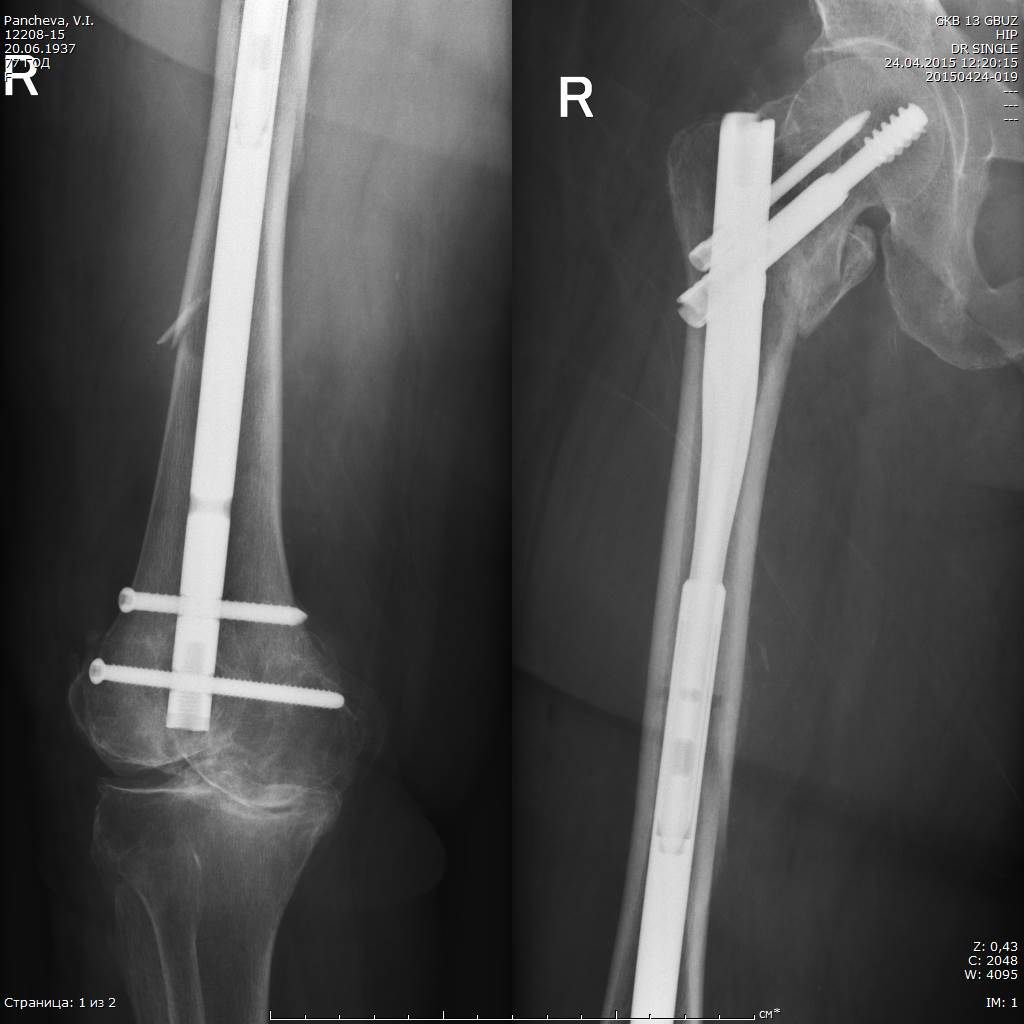

Уважаемые коллеги, наша дискуссия давно вышла за пределы довольно таки узкой темы - темы периимплантных переломов и ушла на круги обсуждения переломов на фоне повышенной хрупкости костей и даже профилактики переломов при остеопорозе. Громадное спасибо!

Однако понятно, что пациентка не может ждать окончания и результатов нашего обсуждения (хотя в такой дискуссии, наверное, главное - это собственно обмен мнениями), просто физически она не выдержит этого. Поэтому она и была прооперирована после недлительной предоперационной подготовки примерно через 24 часа после поступления к нам.

При планировании операции мы с коллегами исходили из следующих посылов:

1. Операция, по возможности, должна быть минимально травматичной и занять наименьшее количество операционного времени. Кровопотеря крайне нежелательна, даже небольшая

2. Операция, по возможности, должна дать пациентке шанс ходить с минимальным использованием дополнительной опоры. Костыли по её кондициям невозможны.

Именно исходя из пункта два был выбран вариант интрамедуллярного ревизионного остеосинтеза.

Вопросы вызывала только необходимость удаления аугментированного клинка, так как такого опыта у нас (в стране?) пока ещё не было. Конечно, в зарубежных статьях я видел, что это возможно, но тем не менее...

А тем не менее клинок, очевидно, благодаря режущим кромкам каждого из отверстий, через которые цемент и попадает в головку и шейку бедра, удалился безо всякого напряжения.

Цемент реально был "срезан" и остался в головке/шейке.

Ну, а установить новый длинный гвоздь такого же диаметра - не проблема, естественно

Новый клинок так же пришлось аугментировать 3 мл специального цемента.

На момент - пациентка достаточно активна, сидит в кровати подолгу, ходит по палате с методистом.